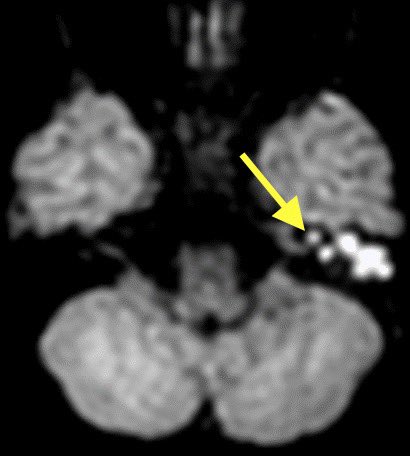

1️⃣DWI shows restricted diffusion of the left mastoid air cells (can be seen in cholesteatoma or purulent mastoiditis)

2️⃣However, additional restriction, enhancement, and loss of normal CSF signal in the left IAC was highly suggestive of suppurative Labyrinthitis

Cholesteatoma with superimposed infection was also complicated by meningitis (seen best at quadrigeminal plate cistern), ventriculitis, skull base osteomyelitis (petrous apicitis) and probably some other itisis that I’m forgetting